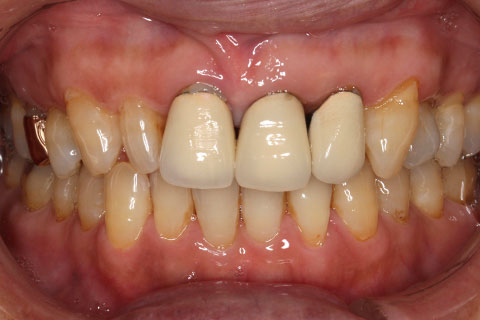

• オールセラミックの症例2

治療前

治療後

年齢・性別

45歳男性

治療期間

2ヶ月

抜歯

なし

治療費

70.4万円

備考

前歯8本の歯列不正によるセラミック治療

治療内容

歯質を削除し、セラミック冠をセメント合着

施術の副作用(リスク)

知覚過敏、歯髄炎、荷重負担